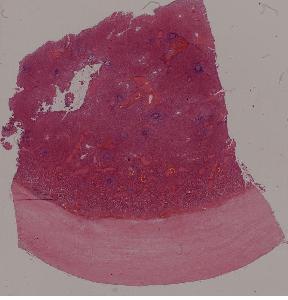

4.脾包膜玻璃样变

高倍视野

低倍视野